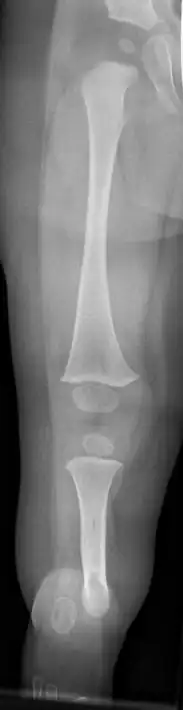

Fibula hemimelia in patient affecting right side | |